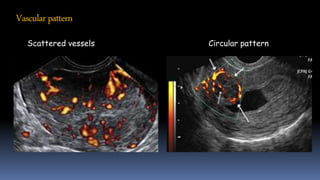

Vascularpattern

Scattered vessels Circular pattern

Predictive of focally growing lesion

High positive predictive value but low negative predictive value

Timmerman 2003 UOG